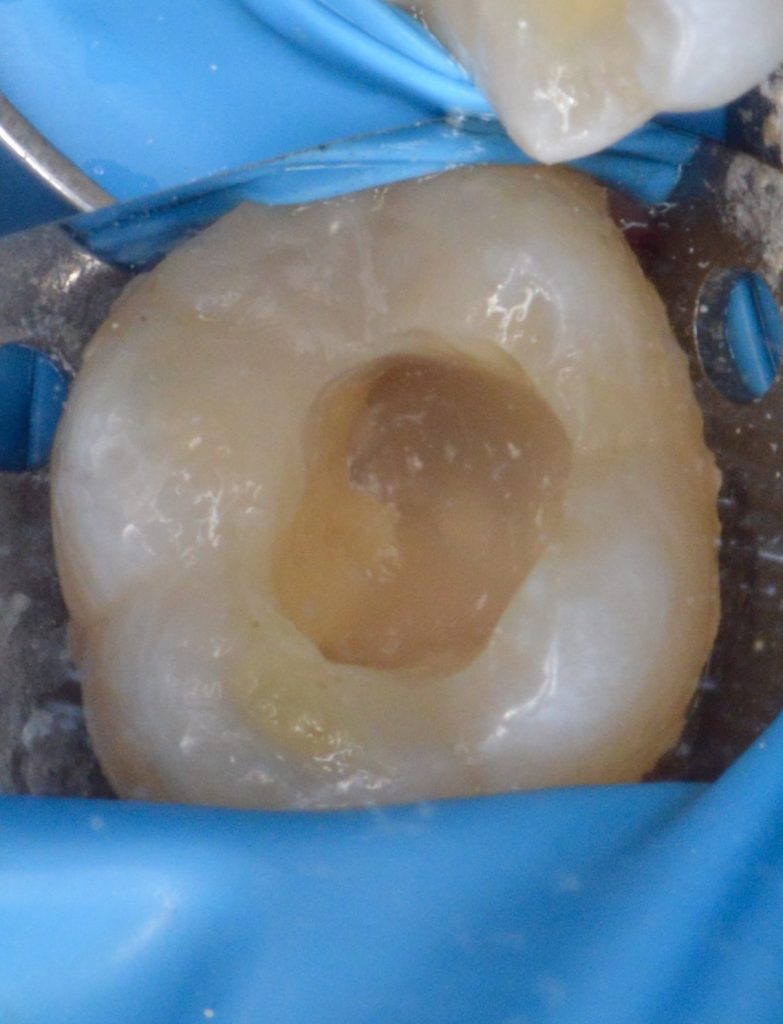

today we’re presenting a direct coronal seal approach using contemporary steps in order to be minimally invasive and keep as much as integral tooth structure as possible, God willing.

(Of course, indirect workflow will help in providing a closer structure to enamel, but the available plan was the direct one in a patient-tailored treatment).